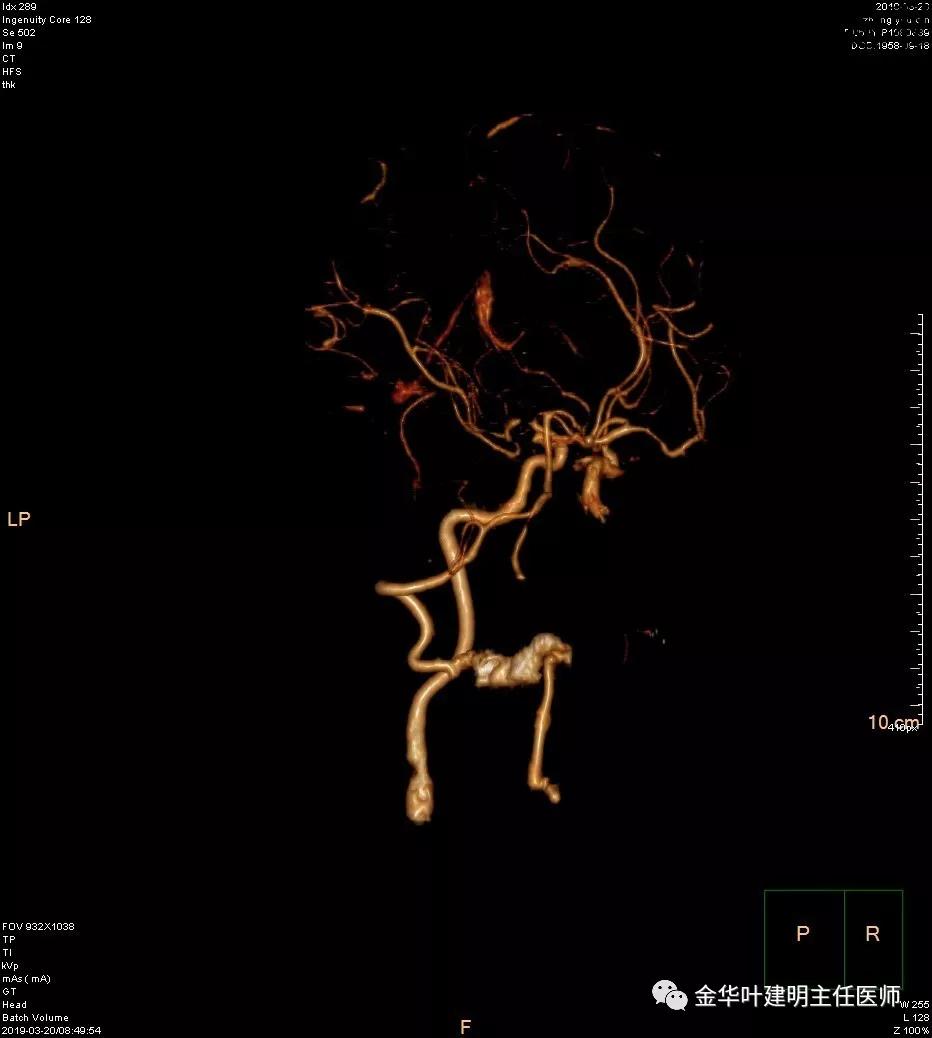

报告提示左侧大脑中动脉M1段及左侧大脑后动脉P1段管腔闭塞。按影像科的建议并请神经内科会诊后,予以行CTA检查。结果如下:

可见其左侧大脑中动脉起始部管腔重度狭窄,右侧大脑中动脉近段管腔也有狭窄;左侧大脑后动脉中远段未见显影。又建议其DSA检查。我们仔细询问章某平时没有神经系统的症状,回忆起来说大概3年前有段时间头昏比较明显,但也没有到大的医院详细检查,后来自行改善。鉴于平时并无明显症状,我们认为其脑血管的病变是慢性闭塞,并已经有侧支代偿。便先请神经外科会诊,会诊后的意见是可以先处理肺部疾病,待情况稳定后再到神经外科进一步诊治。这样,我们便打算为其进行手术。当然因为上叶病灶考虑良性,且位置靠肺外周部位,而下叶病灶考虑恶性,又是中肺叶中央,无法亚肺叶切除,况且病灶大于3厘米,密度虽还是混合磨玻璃,但已经明显偏向实性。所以拟定手术方式是“胸腔镜下左肺下叶切除+上叶楔形切除及纵隔淋巴结清扫术”,当然万一上叶也是恶性,也只能同样是这样的手术方式,全肺切除显然风险过高。